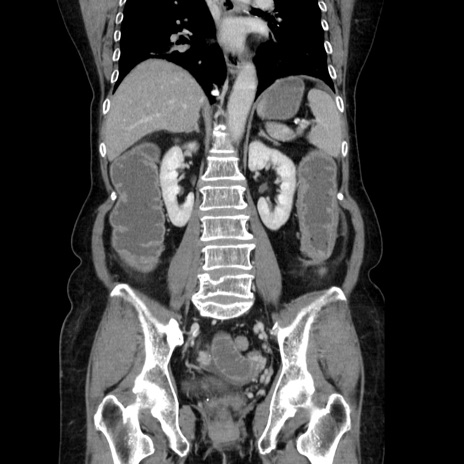

症例5(冠状断像)

【症例】70歳代女性

【主訴】お腹が張る

【現病歴】1週間くらい前から腹部膨満の自覚あり。昨日夜から増悪したため、本日救急外来受診。

【身体所見】意識清明、BT 36.5℃、BP 165/106mmHg、HR 80bpm、SpO2 98%、腹部:膨満、軟、自発痛・圧痛なし、触診にて不快感あり、腸蠕動音:減弱

【データ】WBC 12600、CRP 1.04